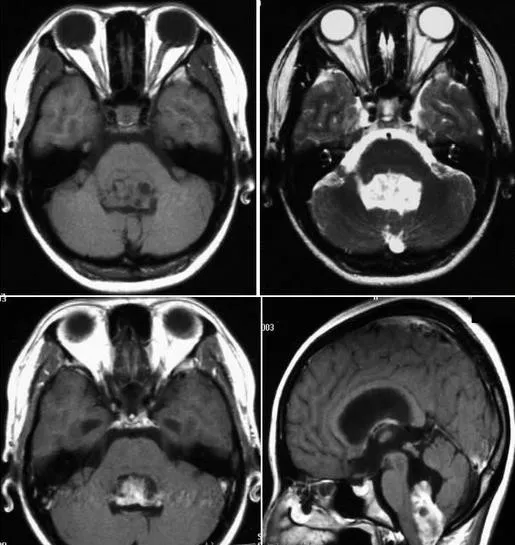

3、CT检查:CT检查位于侧脑室内的肿瘤一般显示不均匀的等或高密度影像,病变同侧脑室可因为肿瘤的占据和室间孔堵塞后造成脑室扩大、变形、肿瘤内可见高密度的钙化灶及低密度的囊变区。后颅凹室管膜瘤表现为中线的占位,经常充满四脑室,并且合并脑积水。肿瘤的密度通常高于正常脑组织,而那些低密度,或等密度的病变很少可能是室管膜瘤。在室管膜瘤中,囊变常见,很容易用CT鉴别。钙化大约占全部病例的44%,并呈弥散或粗糙的结节状,肿瘤强化是典型的表现,肿瘤呈不均匀强化。